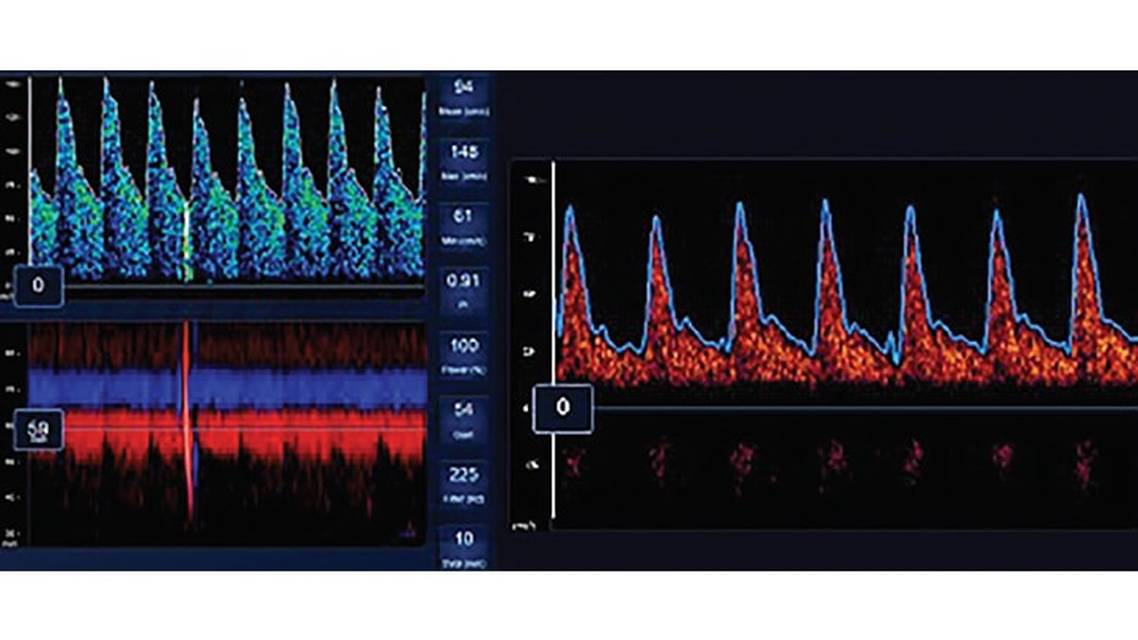

Continuous TCDs may allow for real-time detection of acute large vessel occlusions (LVOs), abnormal autoregulation, emboli, and evolving cerebral edema (Figure 2). In individuals undergoing continuous TCD, an increasing waveform pulsatility index (PI), flow resistance, or newly absent flow may prompt an angiogram to evaluate for high-grade stenosis or occlusion.12 Ultrasonographers may see arterial dilation, which leads to increased cerebral blood flow during acute hypoxic episodes, especially in the vertebral arteries.13,14 These acute changes are reversible after restoring normoxia.13 TCDs of patients on mechanical circulatory devices such as venoarterial extracorporeal membrane oxygenation (VA-ECMO) can show continuous flow without clear systolic peaks.15 A small case series of people with COVID-19 pneumonia who were mechanically ventilated reported the presence of microbubbles after the injection of agitated saline. In this study, the number of microbubbles detected by TCD was inversely correlated with declining PaO2:FiO2, suggesting that pulmonary vasodilation may be a significant cause of hypoxemia in patients with COVID-19.16